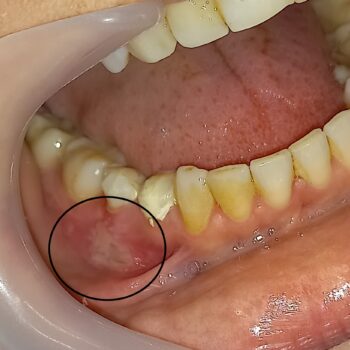

Ερεθισμός του βλεννογόνου κατά τη διάρκεια απονεύρωσης

Σε πολλές περιπτώσεις είναι πιθανόν κατά τη διάρκεια της απονεύρωσης να ερεθιστεί ο βλεννογόνος της γειτονικής περιοχής του δοντιού που θεραπεύεται. Ο ερεθισμός αυτός έχει την κλινική εικόνα που παρουσιάζεται στην παρακάτω φωτογραφία. Ο ερεθισμός αυτός δεν είναι καθόλου ανησυχητικός και προκύπτει όταν δεν χρησιμοποιείται ο κατάλληλος προστατευτικός εξοπλισμός, δηλαδή ο απομονωτήρας. Με το πέρσμα 1- 2 εβδομάδων ο βλεννογόνος ηρεμεί και επανέρχεται στην αρχική φυσιολογική του κατάσταση.